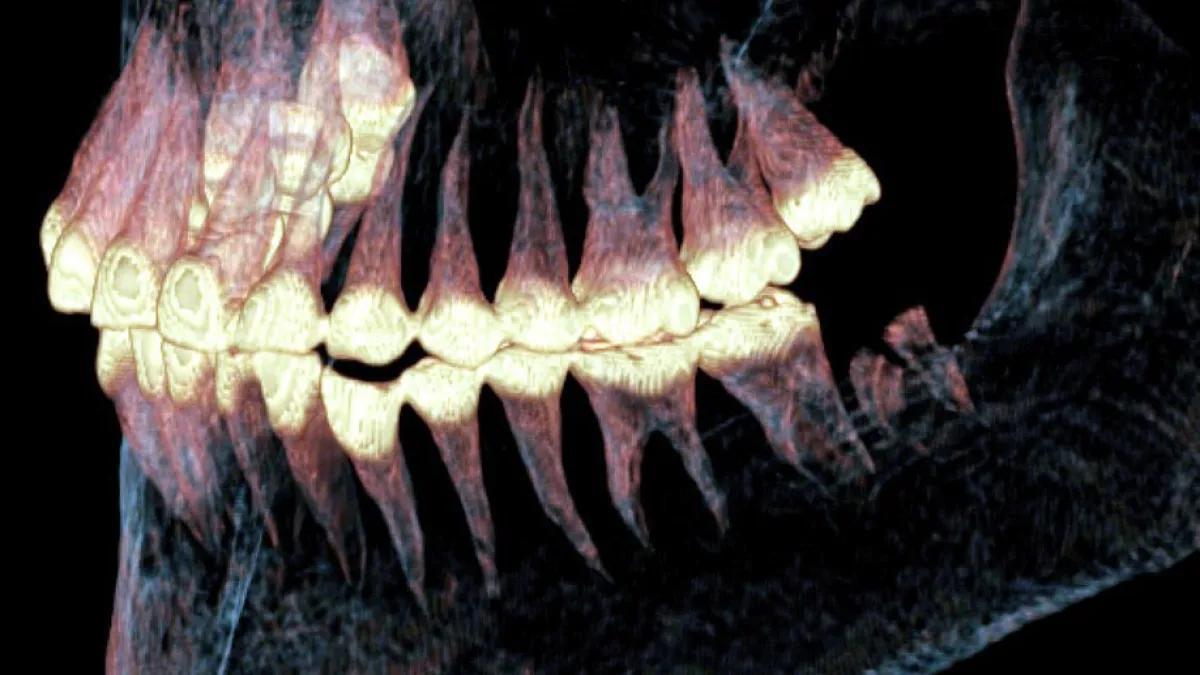

لم تكتشف هذه الجراحة أثناء الفحص المبدئي للمومياء بعد العثور عليها عام 1994، لكن فحصا لاحقا لها استخدم فيه الباحثون من جامعة نوفوسيبيرسك الحكومية في روسيا التصوير المقطعي، سمح لهم برؤية الإصابة وتشخيصها وإعادة بناء نتائج العملية الجراحية القديمة دون الإضرار بالجثة.

وخلال الفحص، وجد الباحثون قنوات رقيقة محفورة في العظام، تحتوي على شعر الحصان أو أوتار الحيوانات لتثبيت المفصل معا، وهذا الطرف الاصطناعي البدائي سمح للمفصل بالتحرك جزئيا، رغم أنها كانت لا تستطيع المضغ من الجانب المصاب بسبب الألم.

وكشف الفحص عن نمو عظام جديدة حول القنوات، مما يشير إلى أن السيدة عاشت عدة أشهر أو سنوات بعد الجراحة، وأنها كانت تمضغ طعامها بالجانب الأيسر لتعويض المصاب.